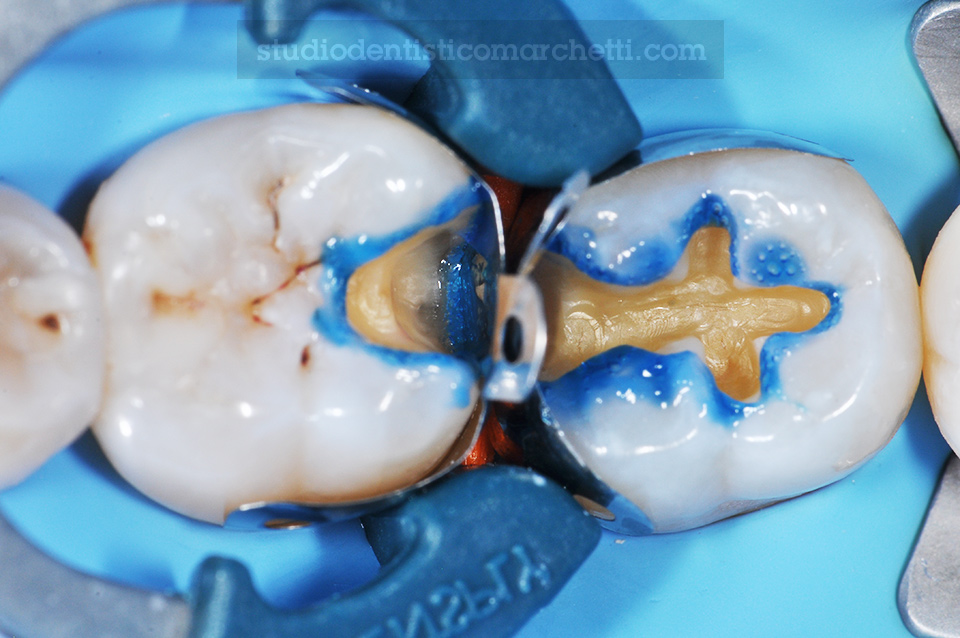

Odontoiatria Conservativa

Odontoiatria Conservativa

Ricostruzioni Dirette Posteriori

Odontoiatria Conservativa